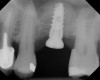

The implant is then delivered and should be well stabilized in the bone. If there is any mobility of the implant, it can either be placed a little deeper (if there is enough native bone) or the implant can be removed and the procedure aborted, in which case it would be a two-stage procedure. This should rarely occur with the tapered designed implant, even with only 2 mm of native bone. Using a bone-level platform-shifting implant (or a tissue-level designed implant) is critical, as the hard and soft tissue will establish a biologic width. If an external hex type of implant is used and the shoulder is placed at the bone level, an expected bone loss of 1.5 mm to 2 mm will occur.24 Figure 10 shows proper bone-level implant depth placement with a platform-shifting design. In this case, a 3-mm healing abutment was placed at the time of surgery to avoid a secondary uncovering surgery, but an implant-level healing abutment could have been placed instead. As can be seen, there was only about 2 mm to 3 mm of native bone height. The membrane was raised about 8 mm to 9 mm. Comparing the radiograph on the day of surgery (Figure 10) to the 6-month postoperative radiograph (Figure 11) shows no loss of native bone, as well as the positive change in appearance of the grafted bone. The 3.5-month CBCT scan (Figure 12) shows good healing of the bone with no coronal bone loss. With minimal native bone present, as in this case, the use of a non-platform-shifting or non-tissue-level implant design could be problematic. After 1.5 mm to 2 mm of crestal bone loss, an external hex designed implant could develop instability with possible implant failure. If a non-tapered implant is used and bone loss occurs during healing, migration of the implant into the sinus could potentially occur. The surgeon can use either a healing abutment or implant-level closure screw over the implant shoulder. With patients who tend to use their tongues to explore or play with the area, or if the area is under a removable partial denture, a closure screw is recommended.